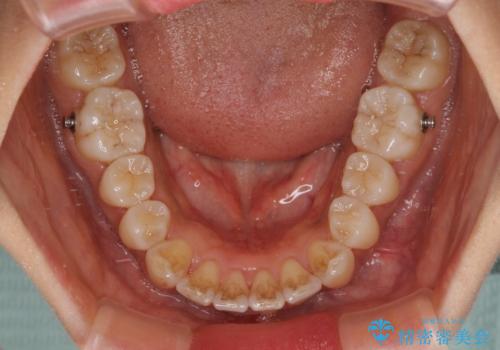

インビザライン単体で改善することも可能ですが、ディープバイトのためインビザライン単体で達成する可能性が低いと考えられたため、カリエール・ディスタライザーという補助装置を併用して、より確実性を上げることとしました。

奥歯の咬み合わせ改善後に、インビザラインにて歯列を整えることとしました。

カリエールディスタライザーを併用したことで、確実かつ短期間で治療を終えることができました。